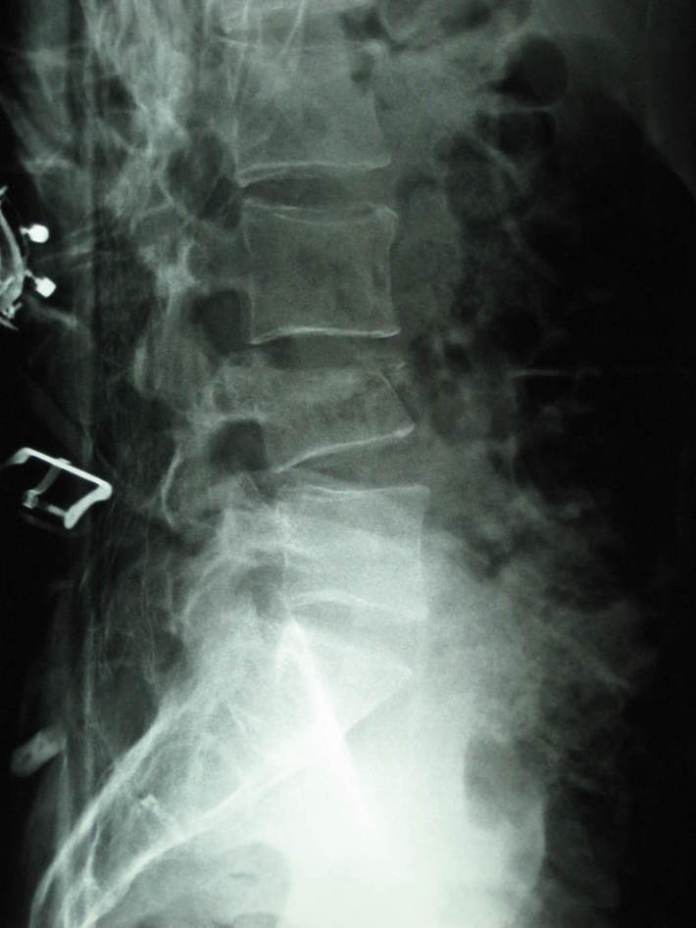

From radrounds.com

Lumbar Compression Fracture (XRay) radRounds Radiology Network What Is A Crushed Fracture the fracture occurs when the bone actually collapses and the front (anterior) part of the vertebral body forms a wedge shape. A compression fracture is a type of broken bone that can cause your vertebrae to collapse, making them shorter. In this type of compression. This generally occurs in the spongy bone in the spine. the main symptom. What Is A Crushed Fracture.